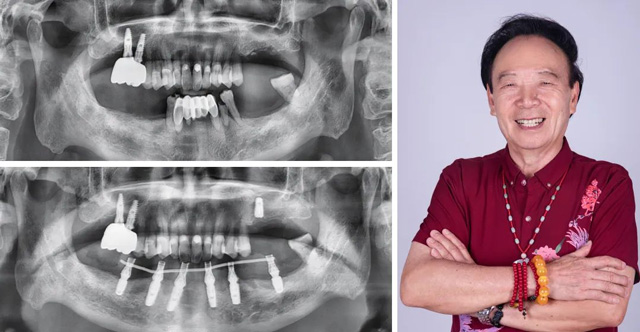

由于张叔叔下颌门牙牙根吸收较严重,保留意义不大,且他本人希望尽快恢复咀嚼功能。新桥医疗团队在对张叔叔的体检报告进行综合评估,确保其能接受手术的情况下,新桥口腔成都衣冠庙院区种植专科主任王旭东决定采用即拔即种的下半口种植修复方案。手术在张叔叔家人的陪伴下顺利结束,同时医院为张叔叔安装了临时牙冠,让他能够在当天就恢复正常饮食。

“半口牙,两个小时就给我整的巴巴适适、舒舒服服,我好像是枯枝发芽般得到了新生,仿佛年轻了20岁!”张叔叔笑道,“当初和玉林那个医生说,能不能拔了就立即种牙,他说我在做梦,现在我梦想成真咯!”